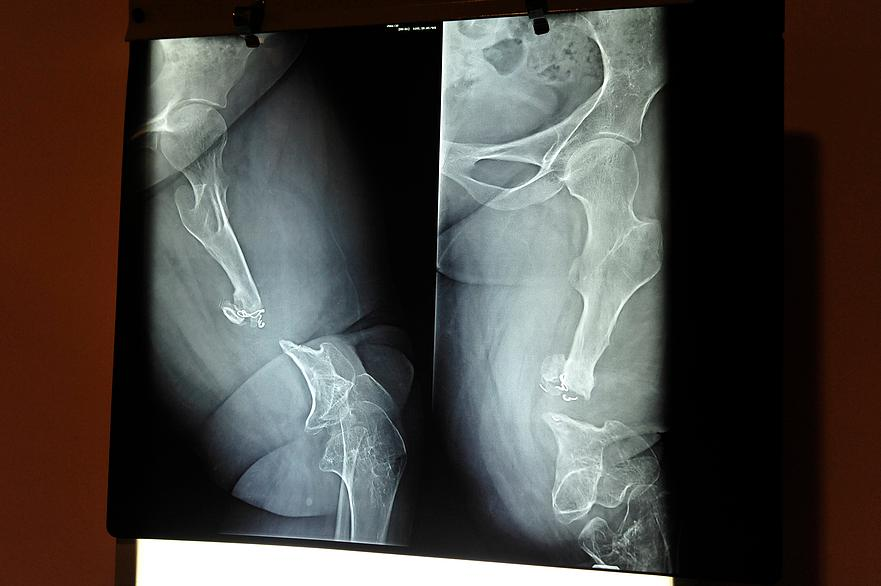

We now have photos!